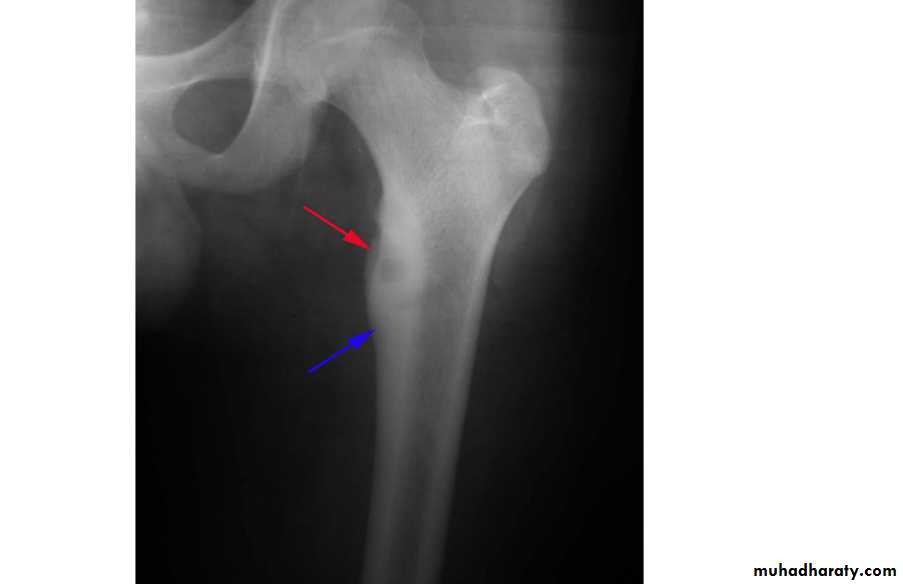

Fibrous dysplasia.

AP radiograph of the proximal femur showing a well-defined expanded lesion with typical ground-glass matrix mineralization and a thick, sclerotic margin .Fibrous dysplasia.

A multilocular, partly cystic, expansile lesion

of the midshaft femur is surrounded by a thick rim of reactive sclerosis.